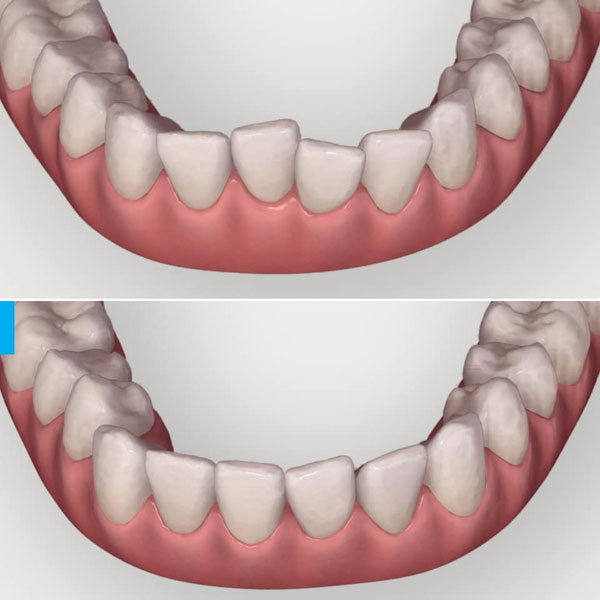

Invisalign can move anterior dental roots quite efficiently with thoughtful planning and meticulous choice and placement of the right attachments. Whether it’s a case of premolar extractions or a simple case that involves merely mesiodistal root movements. This one fell into place in less than 6 months along with the over corrections with no refinement. The lady with a super smile chose to correct only her lower crowding and got reason enough to smile even more!!!

| Midlines spot on despite correcting only the lower teeth |